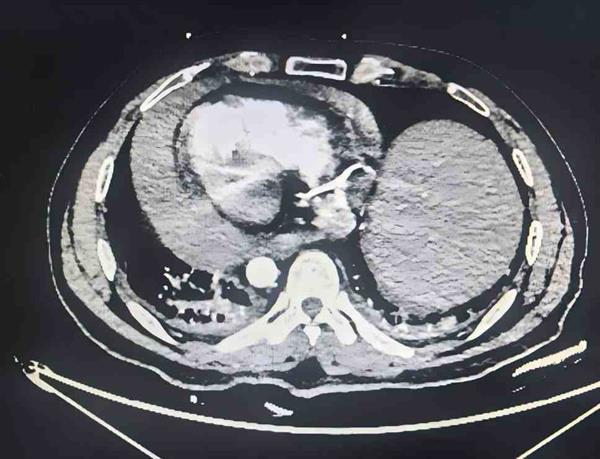

2025年12月22日,黃先生早晨起床后突發(fā)前胸部悶痛,疼痛放射至后背,隨即前往當(dāng)?shù)蒯t(yī)院就診。心臟超聲檢查顯示,黃先生左心室的收縮功能減低(EF40%),舒張功能減退,出現(xiàn)了心包積液。由于黃先生長(zhǎng)期服用阿司匹林、波立維等雙抗藥物,黃先生的胸痛癥狀在4天內(nèi)突然明顯加重。胸部、腹部CT檢查提示,黃先生的心包及心包隱窩有積血,不排除主動(dòng)脈夾層可能,病情危急,當(dāng)即被轉(zhuǎn)運(yùn)至中山大學(xué)孫逸仙紀(jì)念醫(yī)院心血管外科。

心血管外科主任鄭俊猛教授接診后判斷,黃先生心包積血呈進(jìn)行性增加,已出現(xiàn)明顯胸悶、呼吸困難癥狀,若出血持續(xù),極易引發(fā)心包填塞,進(jìn)而導(dǎo)致心臟驟停,危及生命。在藥物止血無(wú)效的情況下,開(kāi)胸探查找到出血源頭并緊急止血,成為挽救患者生命的唯一選擇。術(shù)前CTA檢查顯示存在主動(dòng)脈血腫偽影,這讓病因更加撲朔迷離——是主動(dòng)脈破裂、罕見(jiàn)血管腫瘤,還是其他未知病變?醫(yī)療團(tuán)隊(duì)在協(xié)調(diào)患者安全轉(zhuǎn)運(yùn)的同時(shí),迅速啟動(dòng)急診手術(shù)準(zhǔn)備,待患者到院后即刻完善術(shù)前檢查,一場(chǎng)與時(shí)間賽跑的急診手術(shù)即將展開(kāi)。

影像檢查提示心包積血